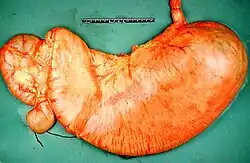

Gastric outlet obstruction (GOO) is a medical condition where there is an obstruction at the level of the pylorus, which is the outlet of the stomach. Individuals with gastric outlet obstruction will often have recurrent vomiting of food that has accumulated in the stomach, but which cannot pass into the small intestine due to the obstruction. The stomach often dilates to accommodate food intake and secretions. Causes of gastric outlet obstruction include both benign causes, such as peptic ulcer disease affecting the area around the pylorus, and malignant causes, such as gastric cancer.